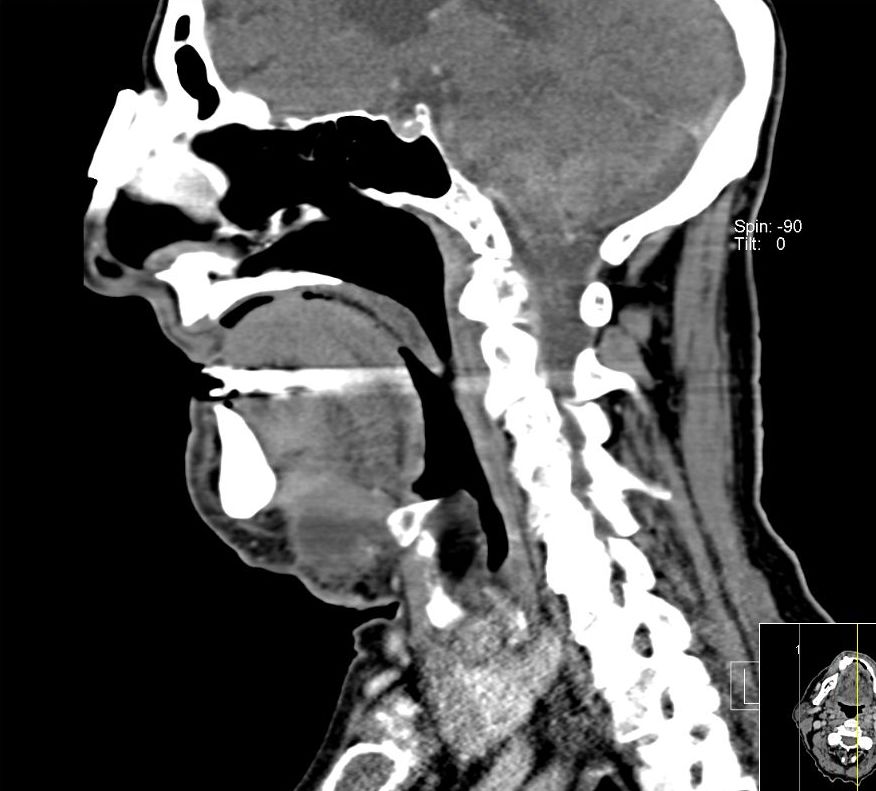

| HNO | 81-jähriger Mann mit einer refraktären Anämie im Rahmen einer Myelodysplasie. Seit einigen Wochen eine rasch wachsende Vorwölbung am Kinn. Intraoperativ infiltrative Gewebeveränderungen, die vom Platysma nicht abzugrenzen sind. Scharfe Absetzung von der Mundbodenmuskulatur. Histologisch zentroblastenänliche Morphologie, CD20 stark positiv, teilweise BCL2-positiv. Keine Expression von S100, Melan A, CK7, EMA, AE1/3, Cyclin D1. CD3 bei nichtläsionalen T-Lymphozyten positiv. |

|||

|

| ||